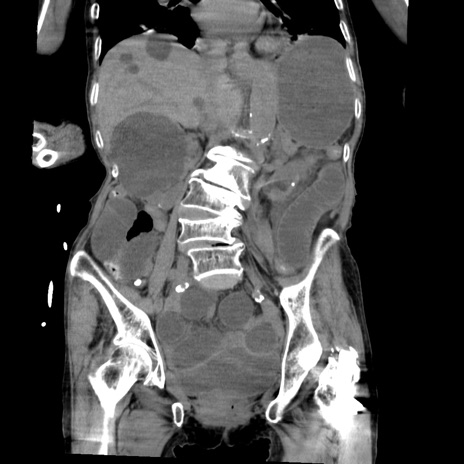

症例27(冠状断像)

【症例】80歳代女性

【主訴】嘔吐、腹痛

【現病歴】数時間前より嘔吐あり。心窩部痛出現し、徐々に右下腹痛あり。その後も数回嘔吐あり救急搬送となる。

【既往歴】左大腿骨頚部骨折手術

【身体所見】腹部は膨隆しているが軟らかく圧痛なし。腸雑音はやや亢進。

【データ】WBC 12000、CRP 19.05